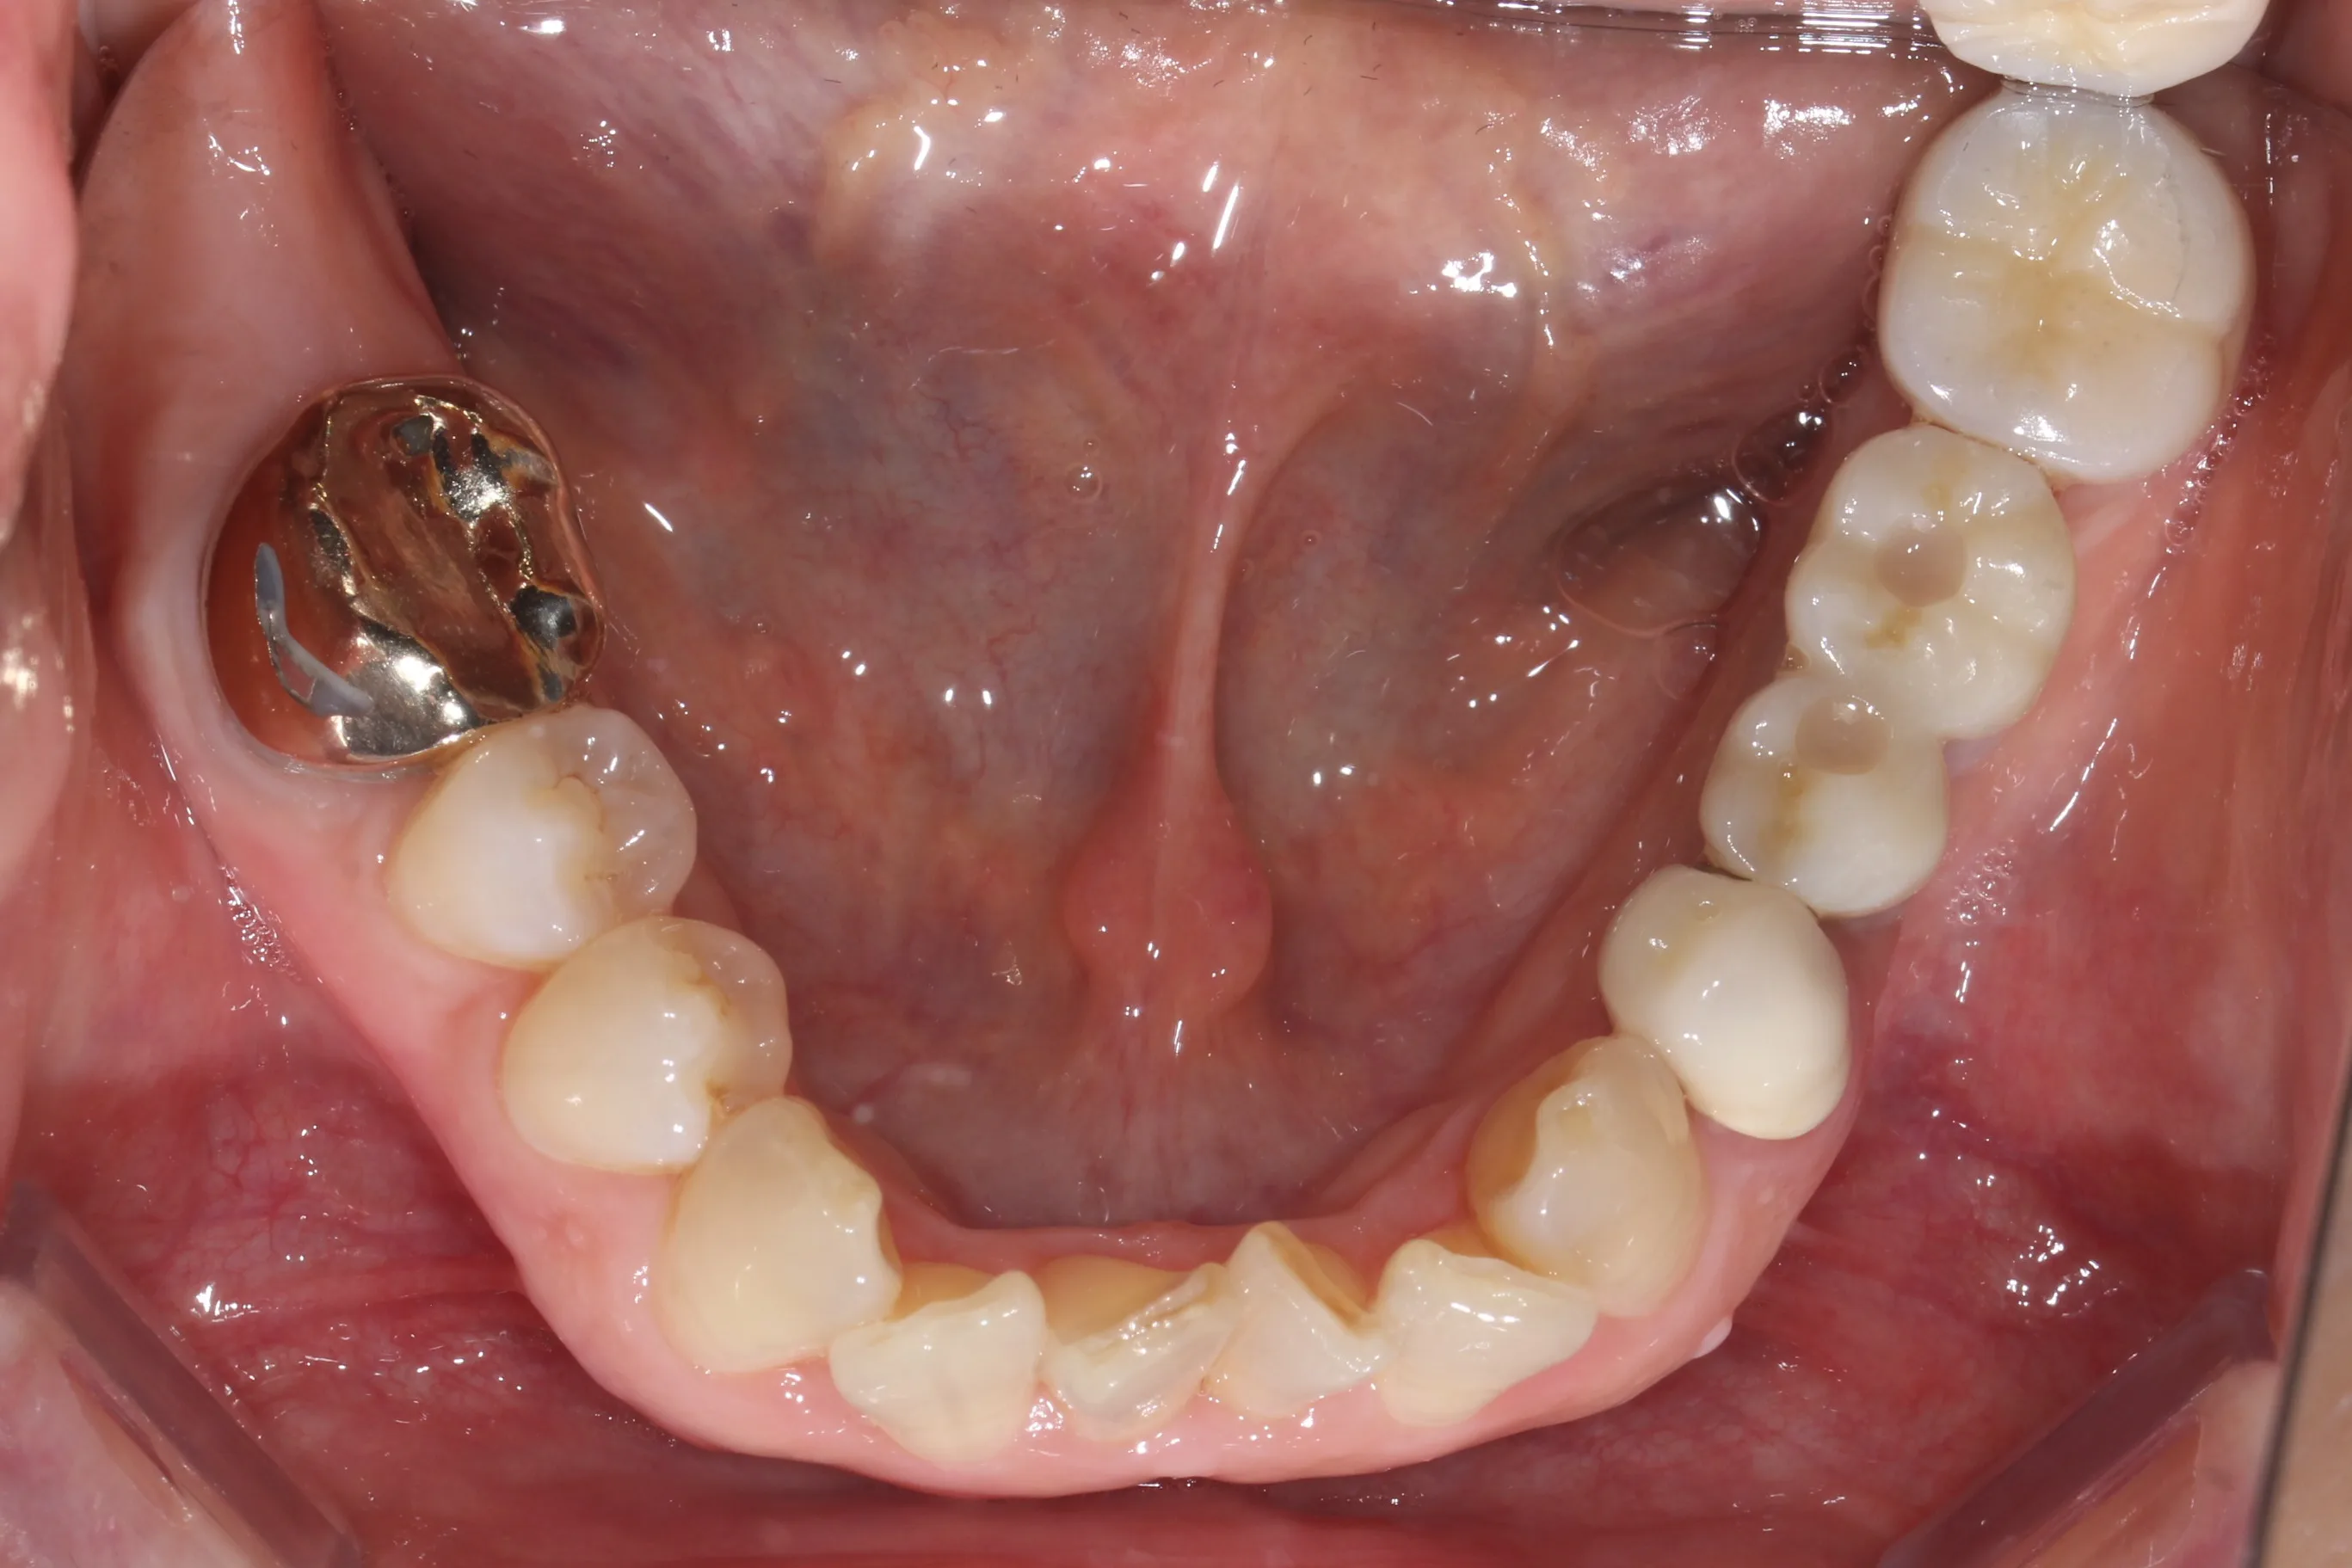

이 환자분은 이미 구강 안에 여러 개의 임플란트와 브릿지 보철물이 있는 상태였습니다. 앞니는 가지런하지 않고, 윗니가 아랫니를 깊게 덮는 과개교합(deepbite)도 있었습니다. 이런 경우 가장 중요한 것은 기존 임플란트와 보철물의 교합을 그대로 유지하면서, 나머지 치아만 가지런하게 배열하는 것입니다.

인비절라인의 디지털 치료 계획을 활용해서, 임플란트와 보철물이 있는 어금니는 움직이지 않도록 고정하고 앞니 위주로만 이동시켰습니다. 덕분에 발치 없이, 고무줄이나 미니스크류 같은 추가 장치 없이도 15개월 만에 치료를 마무리할 수 있었습니다.